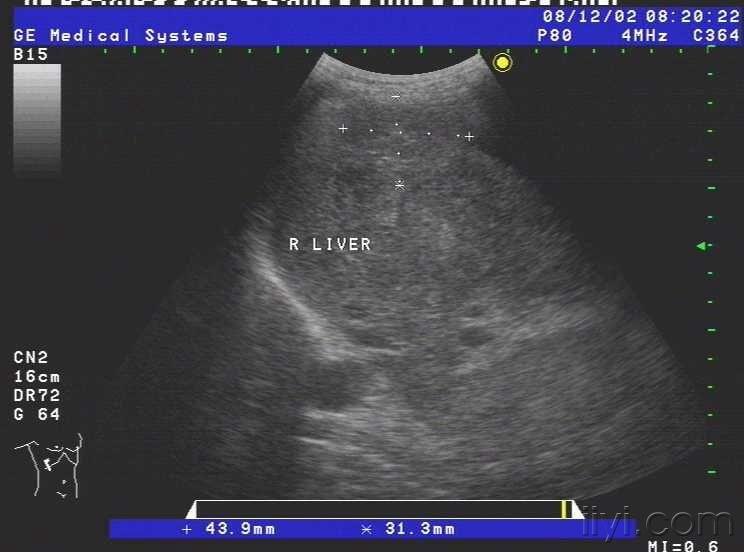

患者女,69岁,病毒性肝炎病史三年余,近半月自觉腹部胀满,来我院就诊,超声查示肝脏被膜不光滑,呈锯齿样,肝内回声不均匀,肝内多发小中等偏强回声团块,大小约1.5cm-3.0cm不等,无明显包膜,境界较清,另于肝右前叶近肝表面见一个大小约4.5cmx2.4cm的椭圆形实性低回声团块,至此处被膜略隆起,团块无明显包膜,伴侧方声影,后方回声增强,内部回声均匀,CDFI未见血流信号.右叶内另见两个类圆形囊性无回声区,肝内管道结构显示不清,肝门脉主干内径约1.1cm.胆囊壁厚1.0cm,囊内透声尚可,脾脏轻度增大,脾门脉无扩张;平卧位腹腔扫查于肝上前间隙肝肾隐窝脾肾隐窝双髂窝均见液性暗区.超声提示:1.肝硬化肝内多发实性团块合并胆囊炎脾轻大及大量腹水;考虑不除外肝癌?